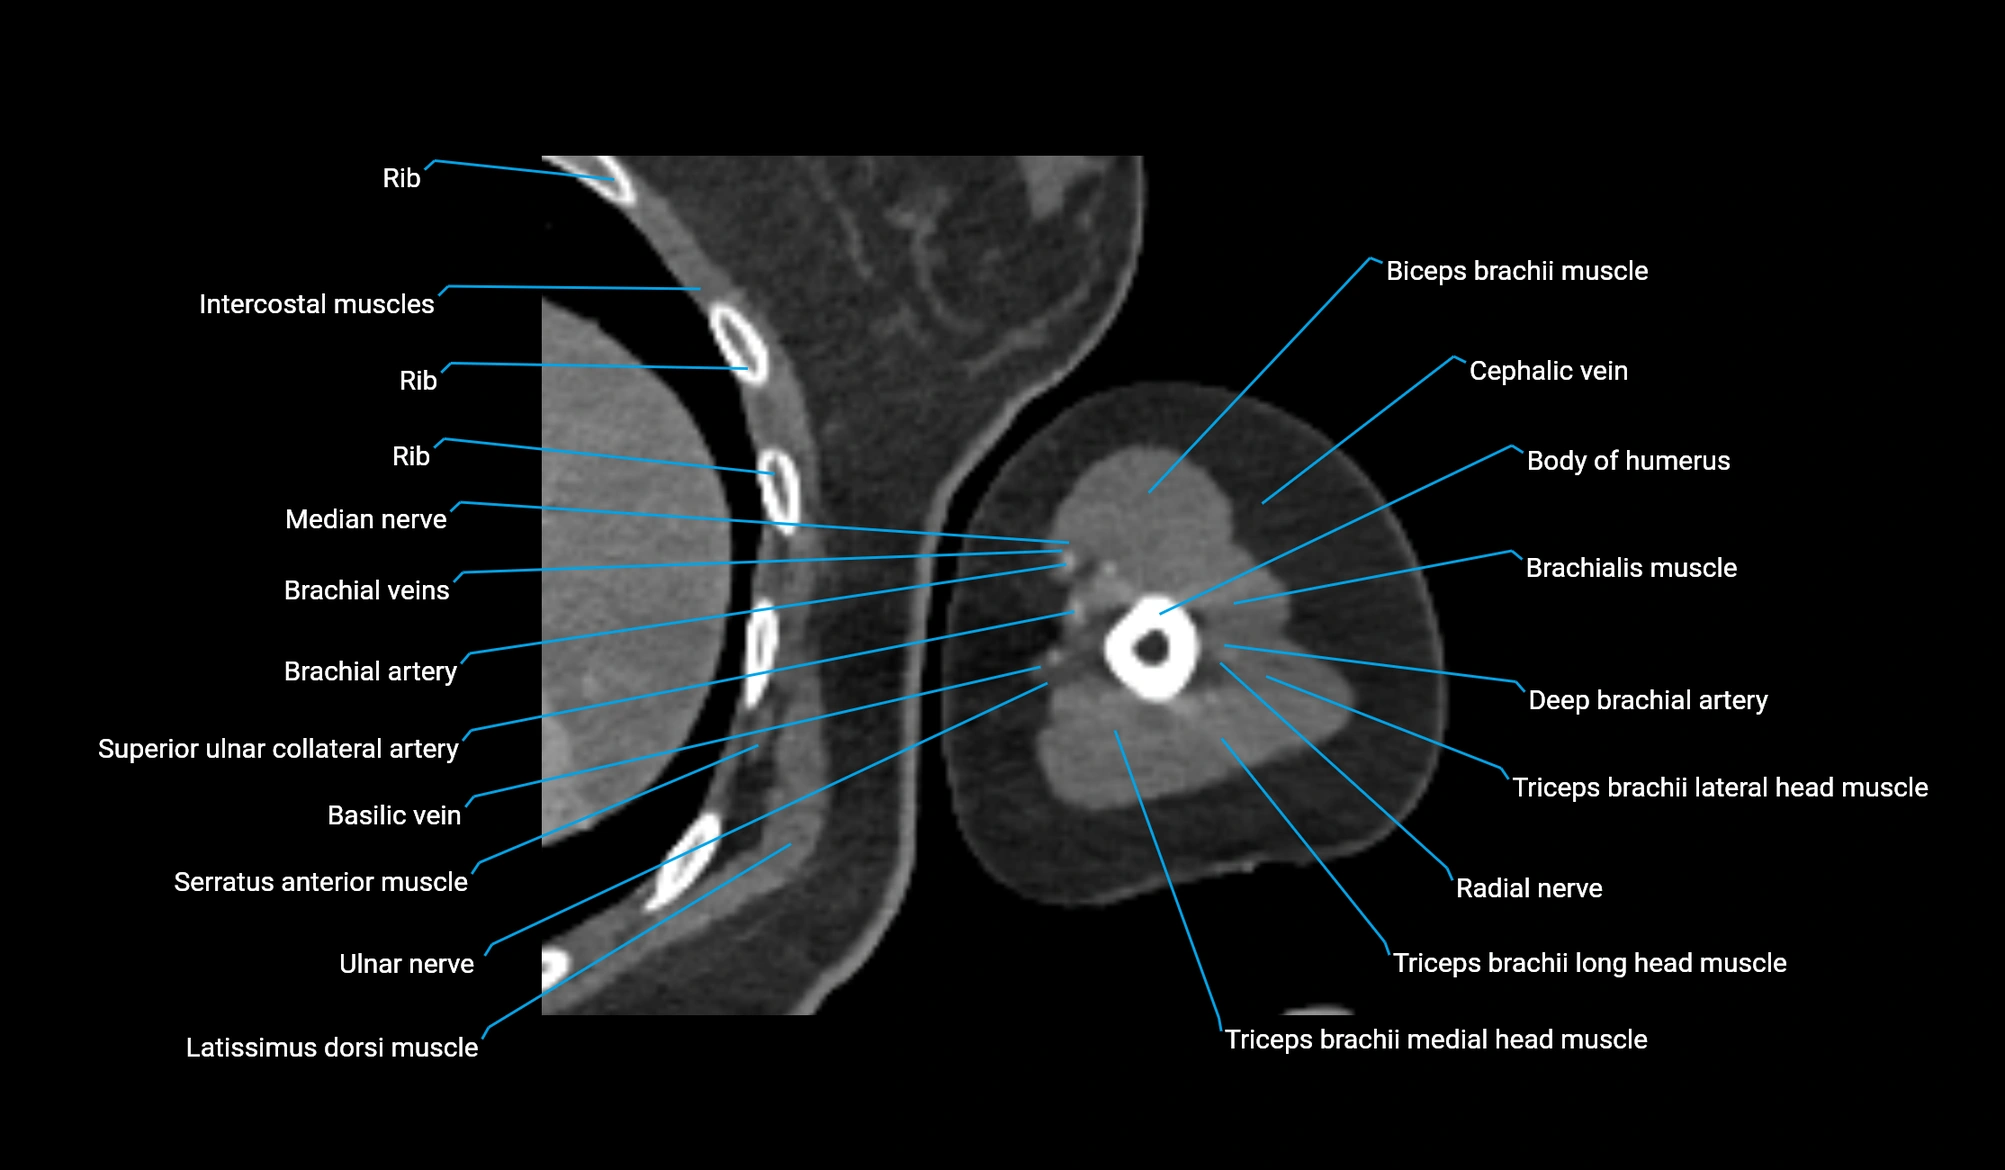

CT image